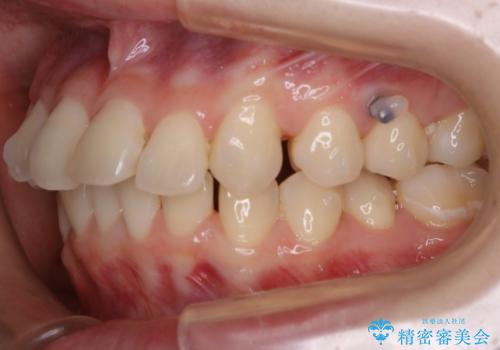

- 笑った時の歯の見え方を治したいとのことで矯正相談にいらっしゃいました。

一見そこまで大きなガタつきはないようにも見えますが、前歯の角度の不揃いや噛み合わせのズレなどから見え方に影響が出てしまっていました。

抜歯は全く必要のないレベルのガタつきだったため、マイクロインプラントを用いて歯全体を後方に移動させていくことできれいな歯並びを獲得することができました。